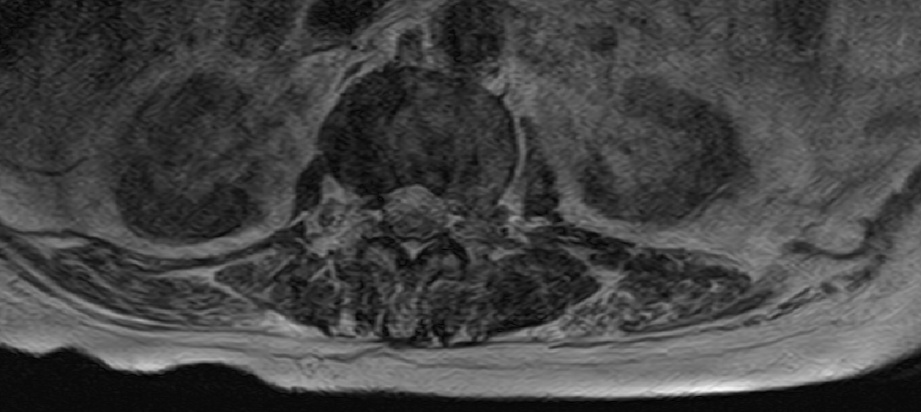

-L Spine MRI

-심한 과호흡 상태에서 검사 시행

-검사 도중 계속 움직임

-Motion Artipact 심하여 scan time 짧게 조정함.

- post L4-5 laminectomy

- flattening of T10 through L2 bodies with partially fatty bone marrow and some sclerotic change

- herniation of discs T10-11 through T12-L1 discs into adjacent vertebral bodies

- L2-3, L3-4 and L5-S1 diffuse bulging discs and ligamentum flavum thickening with indentation of thecal sac and encroachment on neural foramens

- some CSF effacement of L2-3 and L3-4 thecal sac

- partial to circumferential perineural fat effacement of left L5-S1 neural foramen

- decreased T2 signal intensity of discs with osteophytes

1. old T10 through L2 compression fracture with schmorl's nodes

2. L2-3, L3-4 and L5-S1 diffuse bulging discs

3. mild L2-3 and L3-4 central stenosis

4. moderate stenosis of left L5-S1 neural foramen

5. degenerative spondylosis